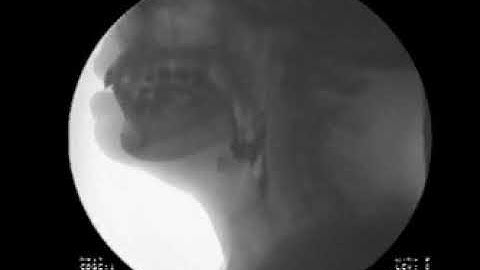

Swallow Study - Solid Texture/Cracker - Modified Barium Swallow Study (MBSS) Lateral View HD